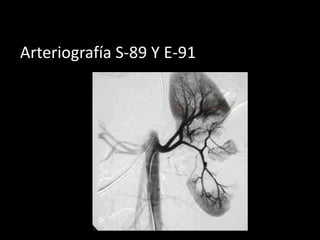

Arteriografía S-89 Y E-91

TAC S-95 Y E-97

•